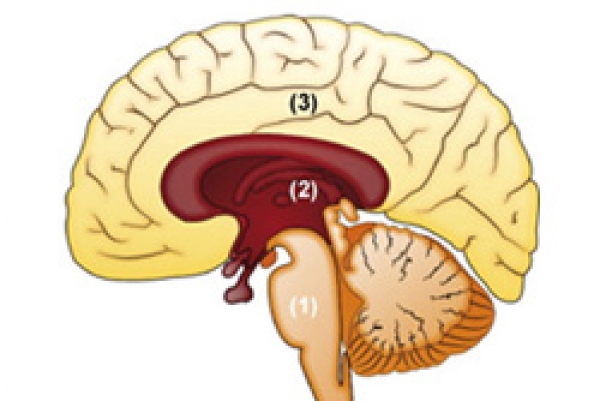

A bél-idegrendszer felépítése

Mint kiderült, az ideghálózatokban igen gazdag, neurotranszmitterektől nyüzsgő emésztőrendszer sokkal többre képes, mint pusztán az emésztés vagy az időszakos gyomorremegés előidézése. Szerkezetileg és neurokémiailag is a bél-idegrendszer egy különálló agyként fogható fel.

A dr. Gershon által 1996-ban „második agy”-nak becézett bélrendszer a nyelőcsőtől a végbélig a maga 9 méteres hosszával mintegy 100 millió idegsejtet tartalmaz – többet, mint a gerinvelő vagy a perifériális idegrendszer. Olyan neuronok és az idegsejtek közötti kommunikációt segítő fehérjék vannak itt, mint amilyenek az agyban is megtalálhatók. Idegsejtjei ugyanazokat a neurotranszmittereket termelik, mint az agy idegsejtjei. Több, mint 30 olyan különböző terméket állít elő, ami az agyban is termelődik. A kutatókat sokkolta a tény, hogy a ’nervus vagus’ idegrostjainak 90%-a a bélrendszerből szállít információkat az agynak, és nem az agyból a bélbe. A bél-idegrendszer saját érzékelésével és reflexeivel felszerelve az agytól függetlenül képes önmagát szabályozni - képes a tanulásra, emlékezésre és érzések létrehozására is.

Ahogy az agy, úgy a bél-idegrendszer is impulzusokat fogad, tapasztalatokat gyűjt és érzelmekre reagál. A bélrendszer falában két idegsejthálózat húzódik, amelyek a központi idegrendszerre jellemző gliasejtek által támogatott. Az idegrostok szoros összeköttetésben vannak, és közvetlen hatást gyakorolnak az emésztés gyorsaságára, a bélfalban található izmok összehúzódására, a bélbolyhok mozgására és a kiválasztásra. Felelős a bélrendszer takarításáért, az immunrendszerrel való együttműködésért (amivel védelmezi a bélrendszert) és a szomszédos szervek, mint az epehólyag vagy a hasnyálmirígy beidegzése is a bél-idegrendszerből történik.